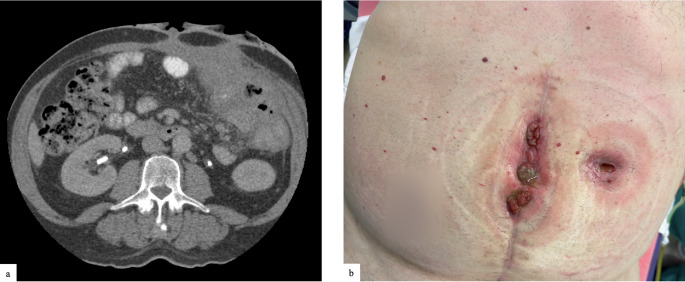

Abstract Image